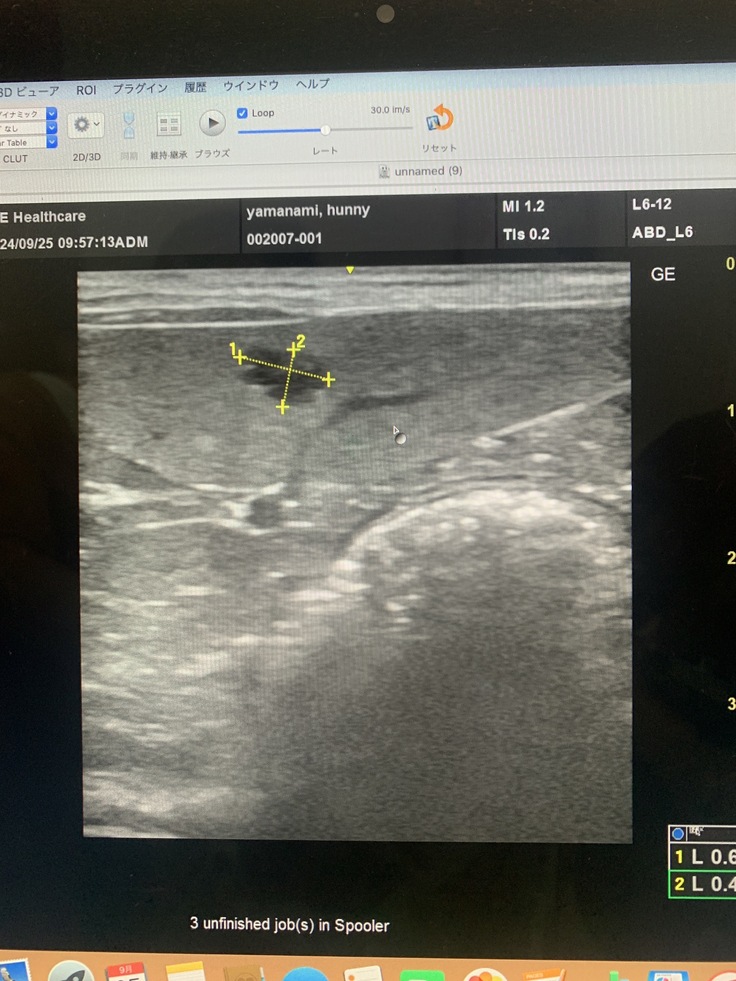

9月25日かかりつけ受診と脾臓の転移見つかる

脾臓にしこり、影→1センチ4ヶ所が見つかった